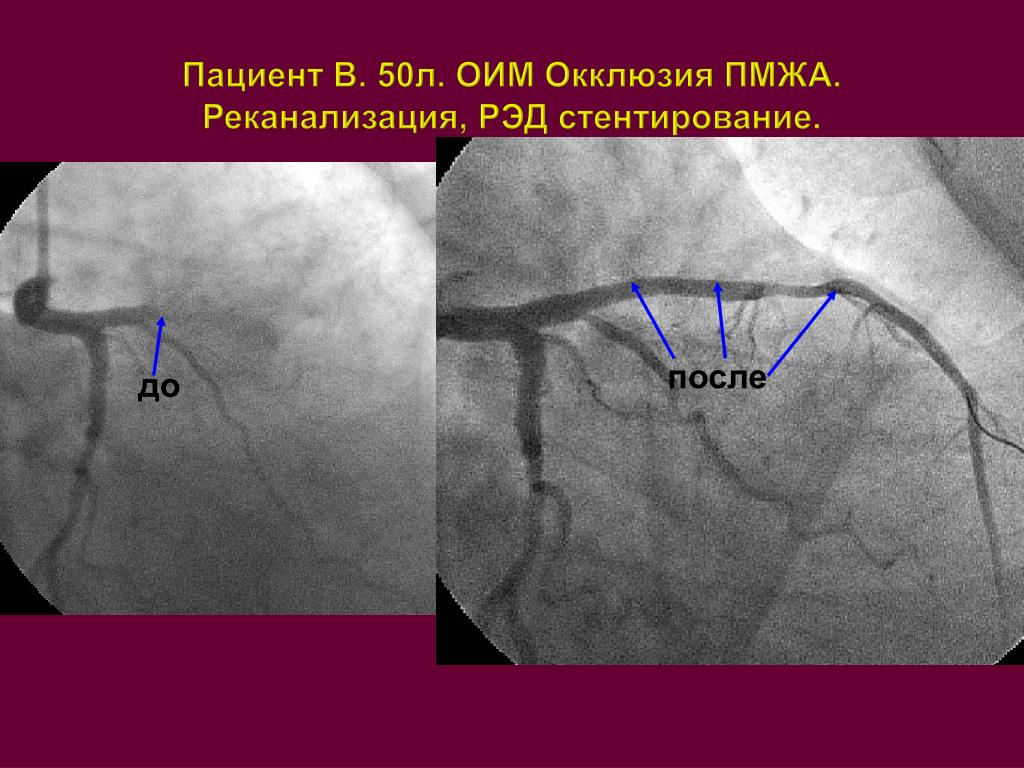

Хроническая окклюзия артерий: причины, симптомы и лечение